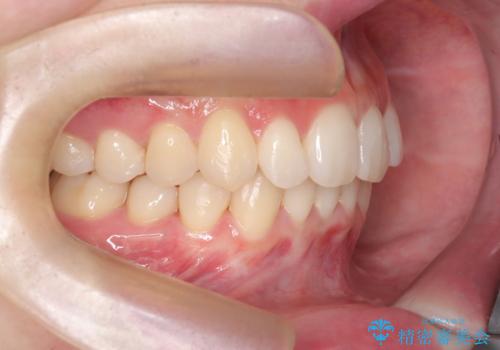

- 患者様は、下顎前歯のガタつきを改善したいとのことで来院されました。診察の結果、スペース不足により前歯が重なっている状態でした。抜歯をせずに並べると前歯が前方に突出してしまうため、下顎の前歯を1本抜歯し、インビザラインで矯正する治療計画を立てました。できる限り追加のアライナーを使用せずに治療を完了できるよう、初回の治療計画を慎重に設計しました。

下顎前歯を1本抜歯し、歯列のスペースを確保。その後、インビザラインを用いて計画通りに歯を移動させ、噛み合わせも整えました。患者様の協力もあり、ゴムかけなどを適切に行い、予定通り1年で治療を完了。追加アライナーを使用することなく、計画通りに治療を終えることができました。患者様からは「思ったより早く終わり、仕上がりにも満足している」と喜びの声をいただきました。